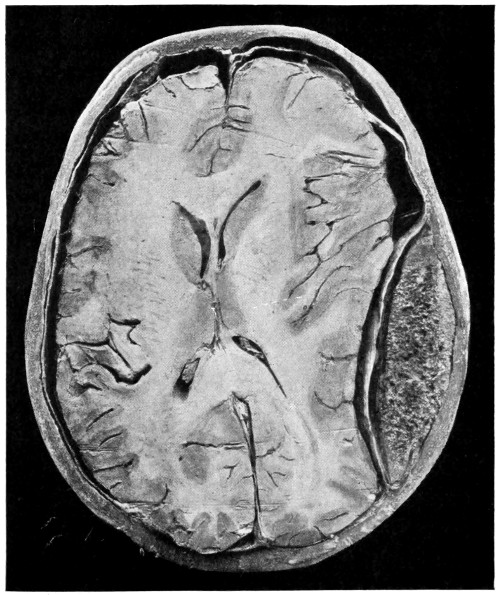

| 75. A large right-sided temporo-sphenoidal abscess | 256 |

| 76. To illustrate the pressure effects of a temporo-sphenoidal abscess | 257 |